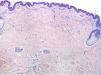

A 77-year-old woman, who was otherwise healthy, presented with multiple white-yellowish millimetric, monomorphic, non-follicular papules, on the posterior cervical region (Figs. 1 and 2). These lesions had been present for several years, and except for mild pruritus, were asymptomatic. Physical examination, including peripheral pulses and cardiovascular evaluation, revealed normal findings. Cutaneous biopsy revealed an ill-defined nodular area in the superficial and mid-reticular dermis, characterized by slight thickening of the collagen fibers and by focally enlarged elastic fibers (Fig. 3). These findings were highlighted in the Verhoeff-Van Gieson staining, which further showed absence of elastic fibers in the papillary dermis (Fig. 4). Calcification of elastic tissue was not seen.

WFPN was first described by Shimizu et al. in 1985. A few years later, the same authors reported this condition in a group of 32 Japanese patients.1 Although initially reported mainly in Japanese men, it also affects Caucasian women, from the 5th to the 9th decades of life.2 WFPN is a rare acquired fibroelastolytic disorder, which presents clinically as yellowish-white round or oval papules that occur more frequently on the posterior neck region, but also on the back, without associated systemic manifestations. Its etiopathogenesis, not fully understood, seems to be related to intrinsic skin photoaging, but is probably multifactorial.3,4 The clinical relevance of this entity lies in its broad differential diagnosis, especially with pseudoxanthoma elasticum (PXE), a genetic disease caused by a mutation in the ABCC6 (ATP-binding cassette sub-family C member 6) gene and is associated with ectopic mineralization of the skin, eyes, and blood vessels.5,6 However, in contrast to the latter, WFPN usually appears late in life, is not associated with systemic complications, and does not require further investigation.3 Histological examination reveals dermal fibrosis consisting of circumscribed areas of thickened collagen bundles in the papillary and mid-reticular dermis, as well as a variable loss of dermal elastic tissue.3,6 Despite its benign nature, WFPN may be cosmetically undesirable and sometimes itchy. Until now, no effective treatments have been established.2 Some topical agents like tretinoin and antioxidants were tried, but improvement was not notable.2,7 Surgical excision may be an alternative choice of treatment in cases with circumscribed lesions.2 Moreover, since WFPN is arguably a feature of photoaging or intrinsic aging, fractional non-ablative laser has been recently tried with good results.2 However, none of the treatments present sufficient evidence in the literature.